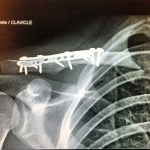

A week later, a day or two after my birthday, I went back to the hospital for surgery on my collarbone and finger. The mission was to nail down the wayward clavicle and reconnect tendons severed in the digital disconnection. One titanium plate and ten screws later, my collarbone was back in a somewhat normal shape, although under X-ray it appeared to contain an entire Erector set. Titanium pins joined the two halves of my finger, but the tendons sought were said to be absent, presumably crushed into subatomic particles in the explosive collision. All in all, it was a great day for modern medicine.